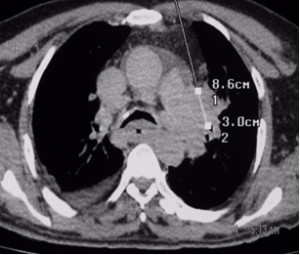

Lesions close to the hilum of the lung like in this case are best biopsied at bronchoscopy. In this case, however, the specimen obtained at bronchoscopy was inconclusive thus forcing a percutaneous biopsy that was only complicated by a small left pneumothorax. I observed the patient overnight in the hospital using periodic chest radiographs and no additional intervention was necessary.